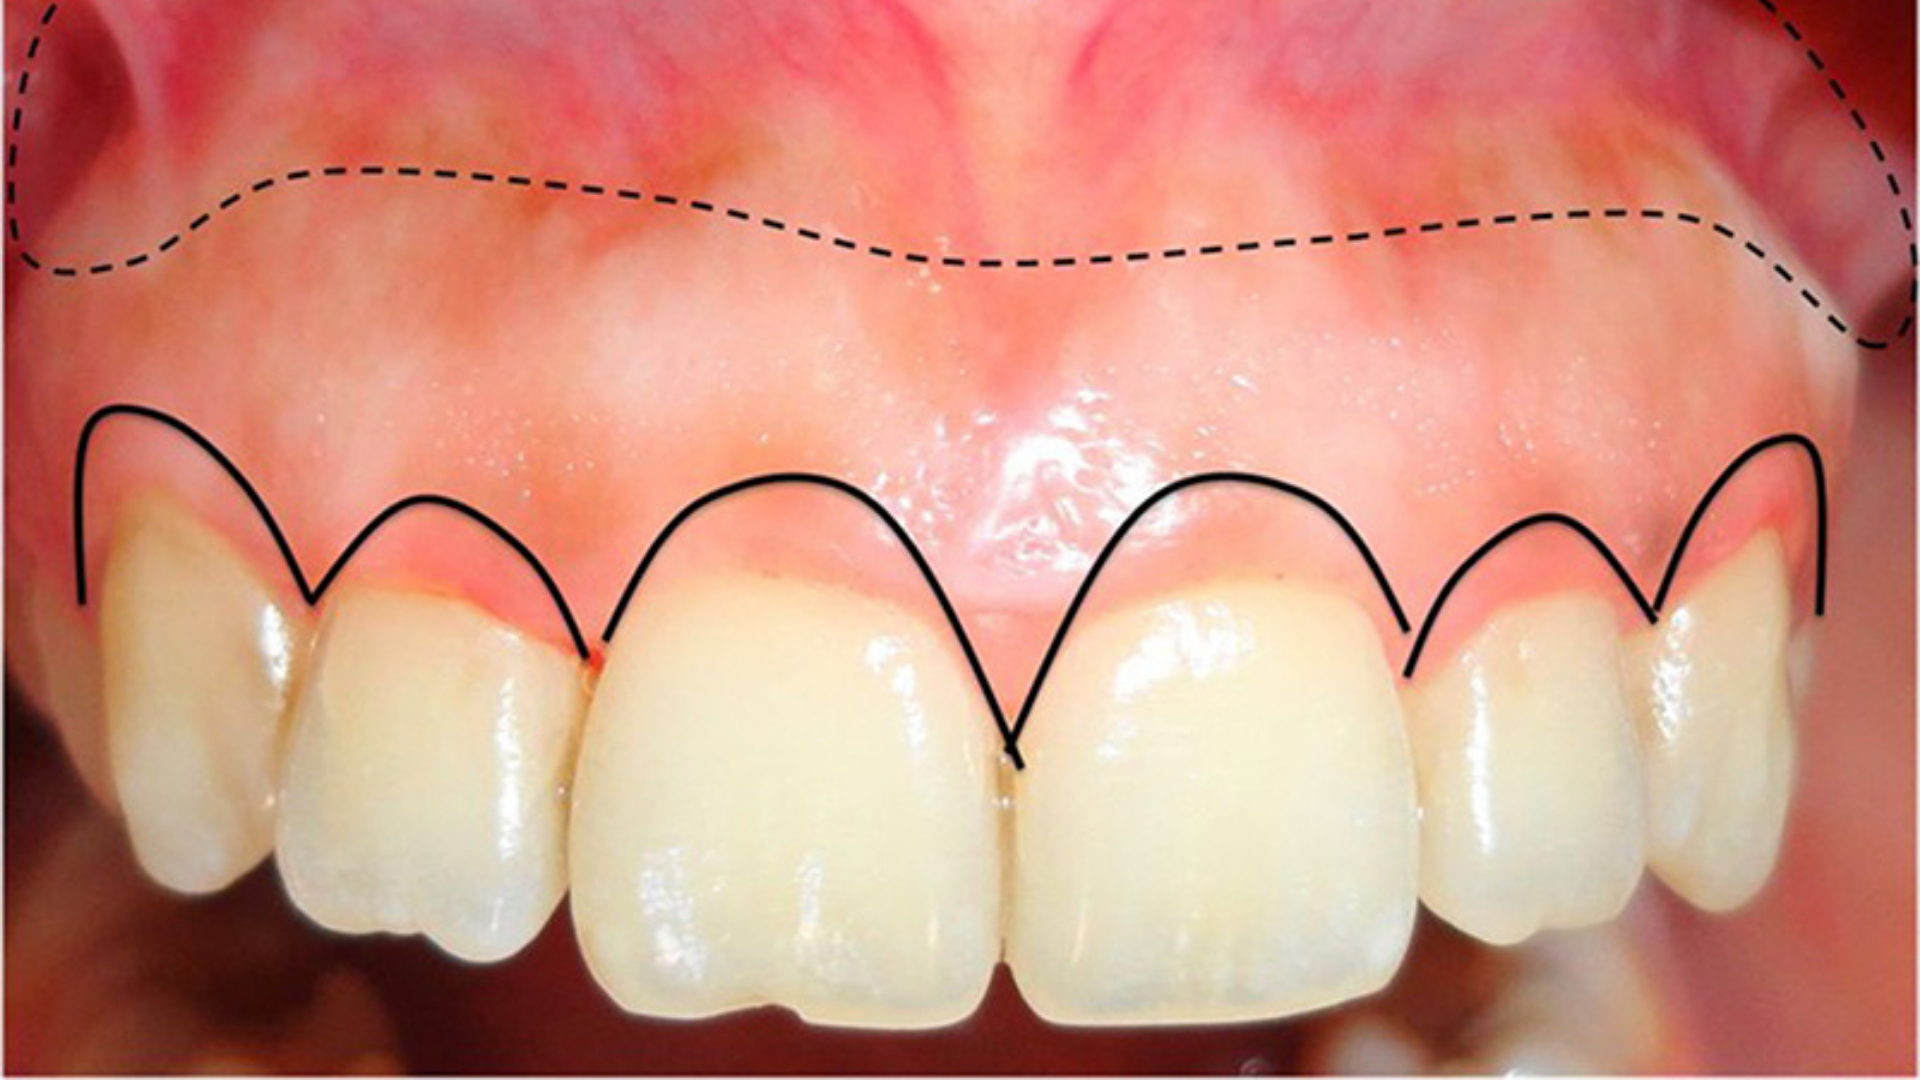

A cirurgia plástica periodontal é indicada para corrigir assimetrias gengivais, sorrisos gengivosos ou retrações que deixam as raízes expostas.

Aumento de coroa clínica: reposiciona o contorno gengival, equilibrando a proporção entre dentes e gengiva.

Gengivoplastia: remodela o contorno da gengiva, proporcionando um sorriso mais harmonioso e natural.